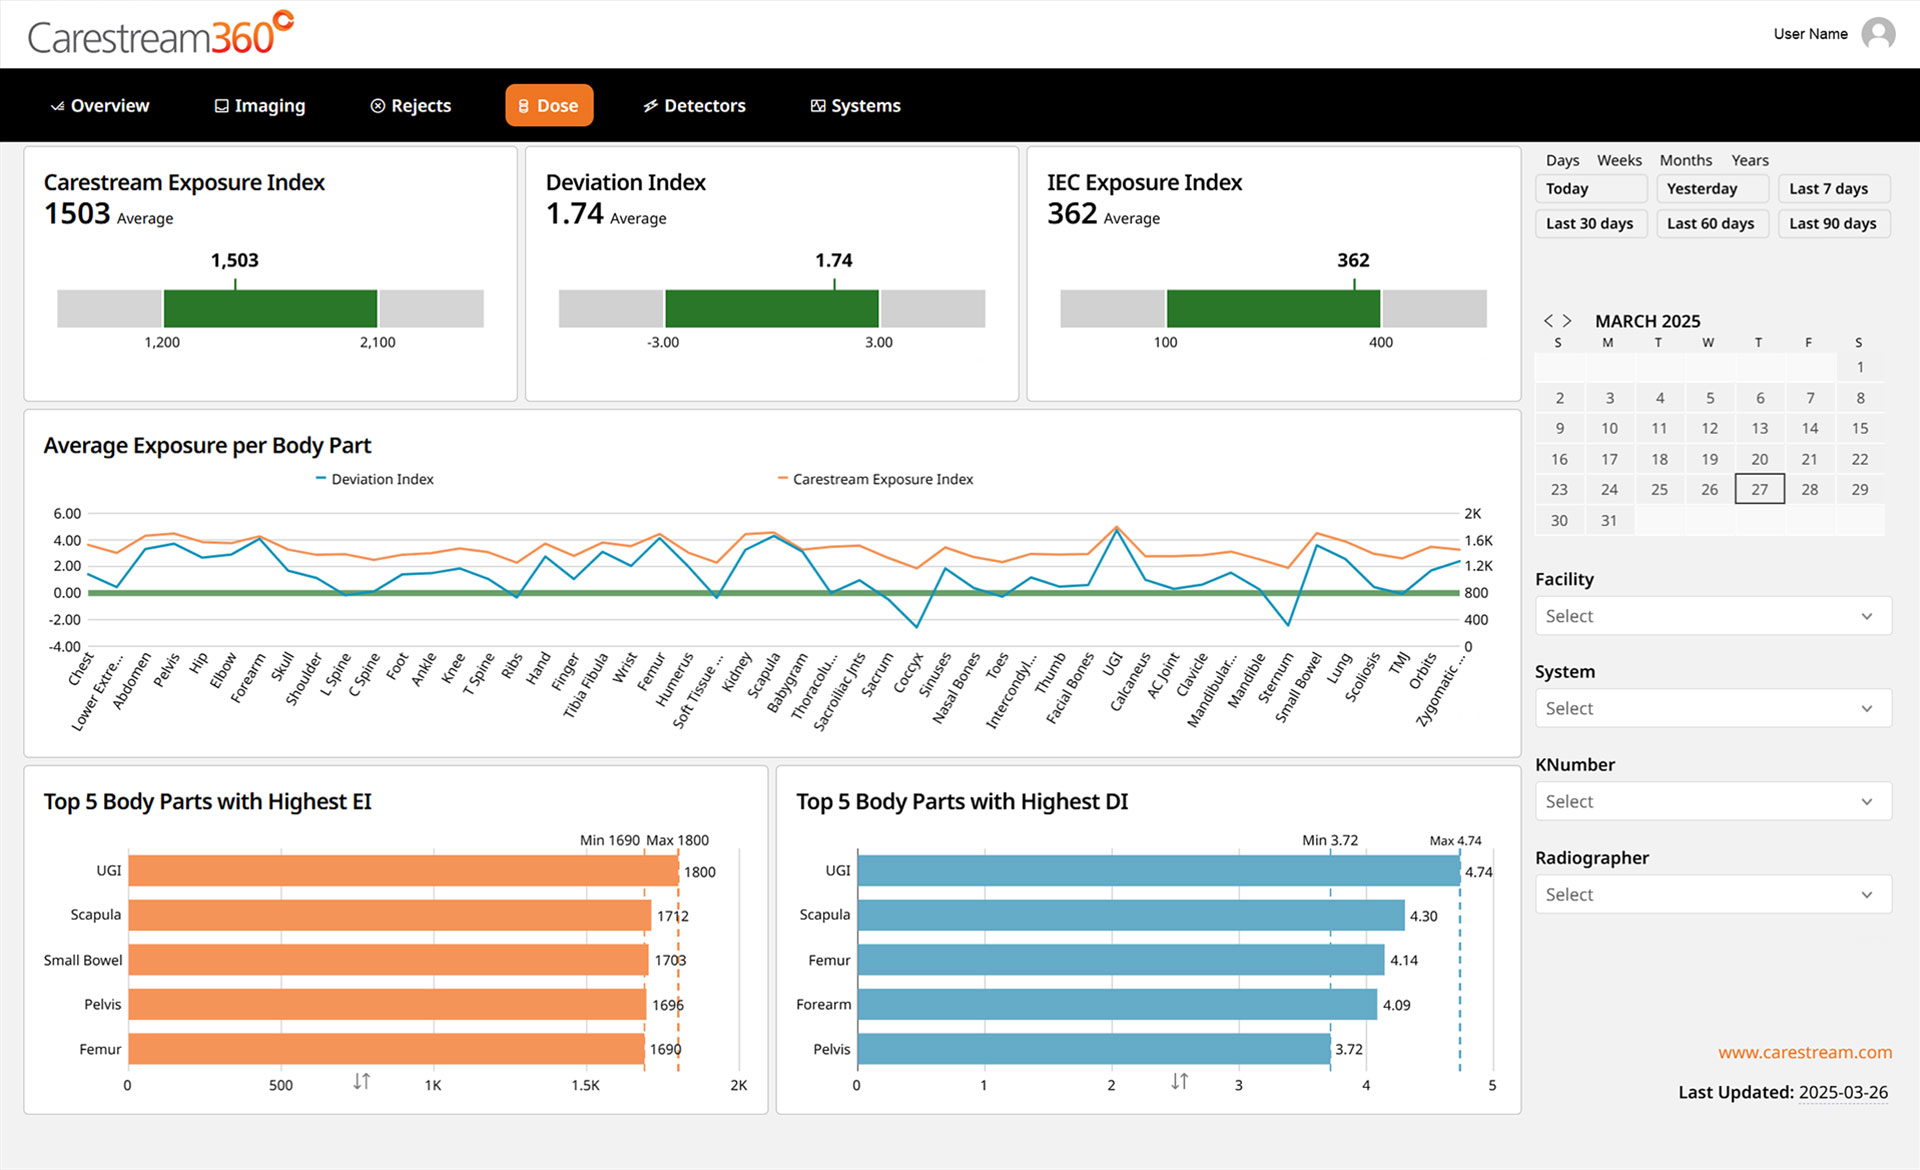

Carestream 360º is an advanced analytics dashboard designed to help radiology departments track key performance metrics, analyze imaging trends, and optimize operational efficiency. It automatically collects critical data from all connected Carestream DR systems and consolidates it into a single, intuitive dashboard, providing a comprehensive view to drive smarter decision-making.

Key Insights to Optimize Performance

Carestream 360º transforms complex performance metrics into clear, actionable insights through a series of intuitive dashboard pages. Designed for efficiency, it helps you: